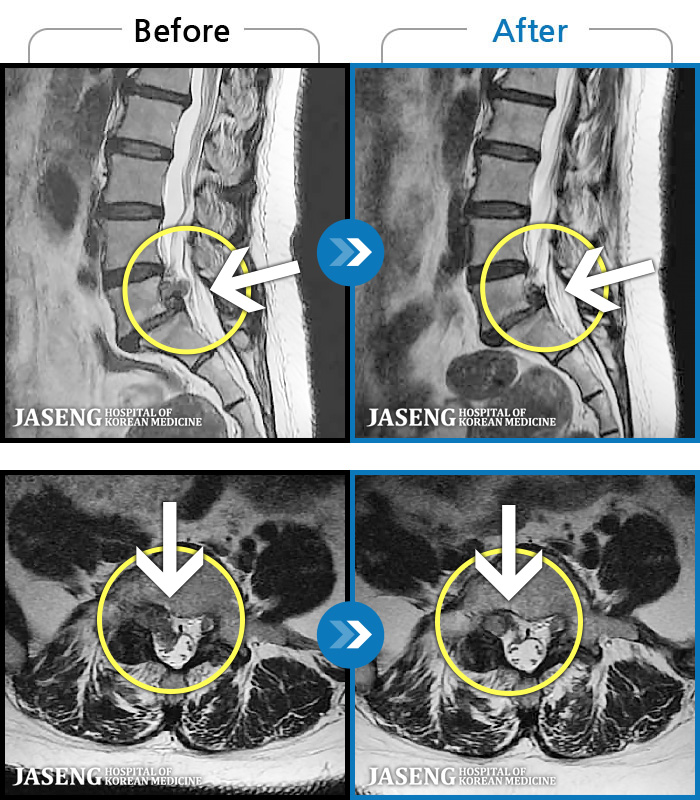

ȯںп Ǹ ǿ ԿǾ, ο ġ ۿ Ƿ ġḦ Ͻñ ٶϴ.